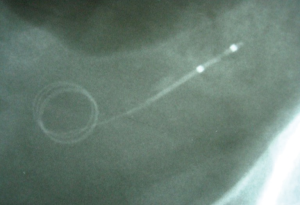

In the setting of acute ureteral obstruction secondary to stone disease, it is advantageous for a ureteral stent to create maximal dilatation while occupying as little space as possible within the lumen of the ureter, to facilitate stone passage and relief of upper urinary tract obstruction. The Microstent (PercSys) is a 3 Fr stent that is based on a guidewire with a distal bladder anchoring coil and a novel proximal film anchoring mechanism that anchors in the ureter immediately proximal to a ureteral calculus (Figures 2,3). The potential risk of using a smaller stent is that it may not provide adequate drainage of the obstructed system. To determine if this smaller stent drained well, Lange et al. performed a study with an in vitro and ex vivo porcine model to measure mean flow rates through obstructed and unobstructed ureters with either a 3 Fr Double-J stent (Cook), 3 Fr Microstent (PercSys) or standard 4.7 Fr Double-J stent (Cook) (16). They found the 3 Fr Microstent demonstrated drainage equivalent to the standard 4.7 Fr Double-J stent, in both in vitro silicone and ex vivo porcine obstructed urinary models. Further studies are needed to examine whether there are improved rates of stone passage with the Microstent, given its minimal occupation of space within the ureter. A clinical trial is ongoing at our institution to evaluate the use of the Microstent in patients with acutely obstructing ureteral stones. This stent can be delivered similarly to a guidewire through a flexible ureteroscope directly into the ureter. Removal of the proximal portion of the Microstent inside the scope then deploys the proximal anchoring film inside the ureter and releases the stent. This novel stent may prove useful in relieving acute obstruction caused by ureteral stones.